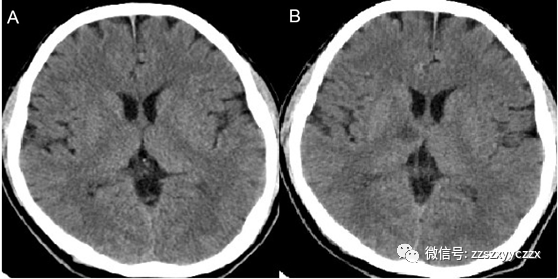

头颅(2020.08.17)(图1-A):1.颅脑CT平扫未见明显异常。胸部CT(2020.08.17)(图2):1.双肺小叶间隔增厚,右侧胸腔积液,心脏增大,心包积液,考虑肺水肿?建议进一步检查;2.双肺下叶少许慢性炎症;3.主动脉硬化。心电图:窦性心律,67次/分,电轴右偏,广泛前壁心肌梗死(时期待定),ST-T呈缺血损伤型改变。2020-08-17 08:01肌钙蛋白I:1.25 ng/ml。随机血糖:7.9 mmol/L。

图1:A.2020-08-17颅脑CT平扫未见明显异常。B.2020-08-18复查头颅CT示右侧丘脑低密度,考虑脑梗死。